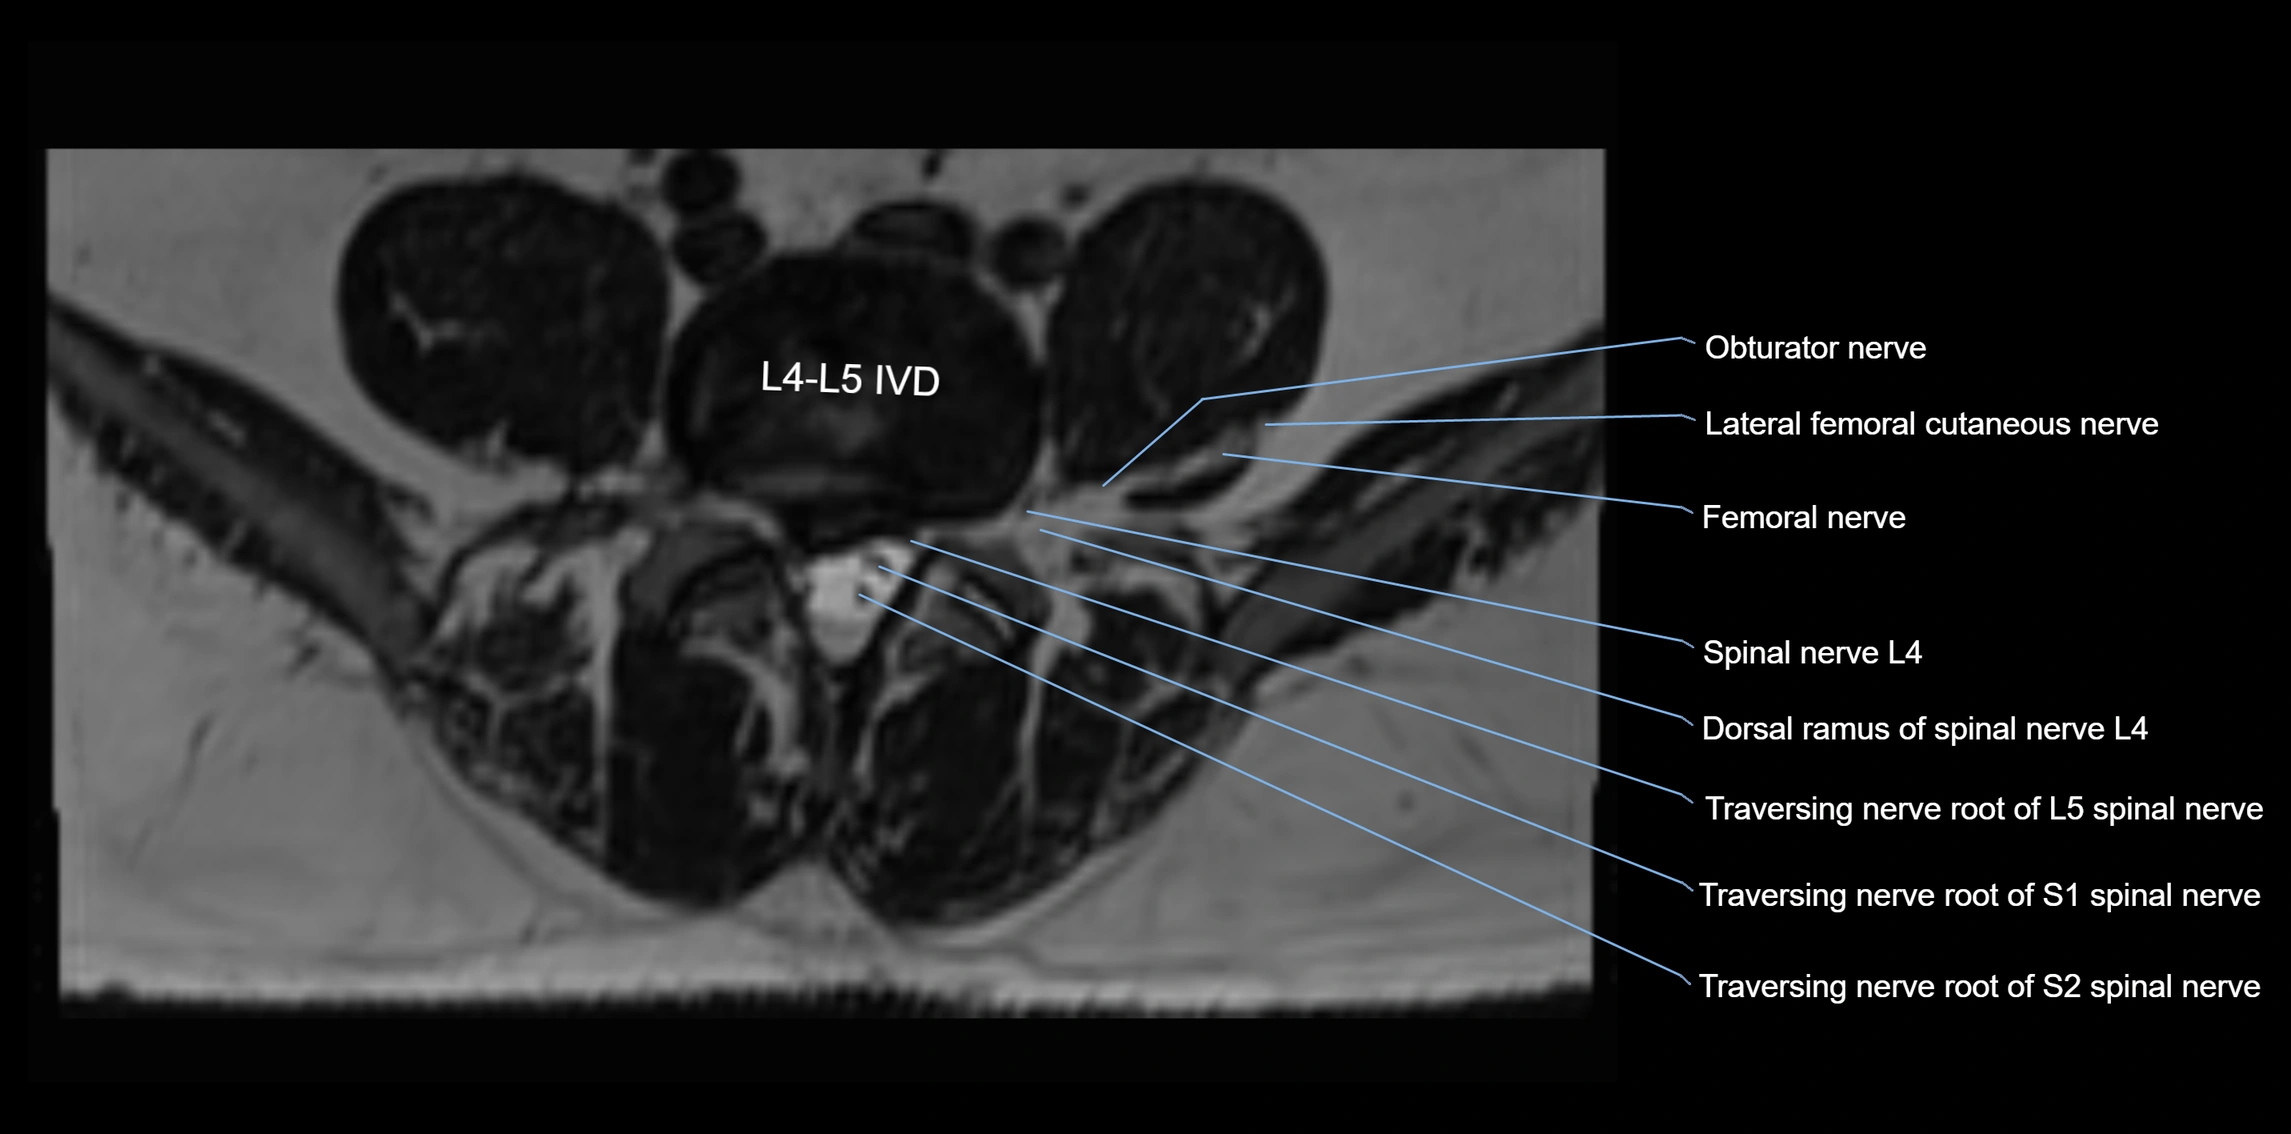

MRI Appearance

T1-weighted images:

• Nerve appears as a very thin low-to-intermediate signal intensity structure

• Surrounded by bright fat, aiding visualization

T2-weighted images:

• Nerve shows intermediate to mildly hyperintense signal compared to muscle

• Pathological involvement appears brighter

STIR (Short Tau Inversion Recovery):

• Normal nerve appears dark

• Inflamed or entrapped nerve appears bright hyperintense

T1 Fat-Sat Post-Contrast:

• Normal nerve enhances minimally

• Pathologic nerve (neuritis, entrapment, tumor infiltration) shows focal or diffuse enhancement

3D T2 SPACE / CISS:

• Nerve appears intermediate to mildly hyperintense compared to muscle

• Surrounded by bright fat or CSF, improving visualization

• Best sequence for mapping small pelvic nerves such as the anococcygeal